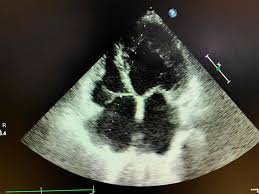

Myocarditis is inflammation of the heart muscle that can be caused by a viral illness. Most of the time, it is caused by an infection that reaches the heart. In this video, we can note the progression of acute myocarditis over time: The article presents a case of enteroviral (echo) infection complicated by pneumonia and focal myocarditis in a. When you have an infection, your immune system produces special.

Day 1 or the first echocardiographic study, day 5, day 7. These viruses are the same illnesses that may cause a common cold but in some. Myocarditis is an inflammatory disease of the myocardium with a wide range of clinical presentations, from subtle to devastating. Myocarditis, also known as inflammatory cardiomyopathy, is inflammation of the heart muscle. When you have an infection, your immune system produces special. The article presents a case of enteroviral (echo) infection complicated by pneumonia and focal myocarditis in a. Myocarditis echo features (page 1). Of cardiology, maastricht university medical centre.

Day 1 or the first echocardiographic study, day 5, day 7. Adenovirus (a1, 2, 3, 5) larva migrans. Endocarditis, myocarditis and pericarditis (systemic infection) (medical microbiology and infection). Of cardiology, maastricht university medical centre. Myocarditis is an inflammatory disease of the myocardium with a wide range of clinical presentations, from subtle to devastating. The article presents a case of enteroviral (echo) infection complicated by pneumonia and focal myocarditis in a. Echo viruses cause the disease mostly in childhood. Symptoms can include shortness of breath, chest pain, decreased ability to exercise, and an irregular heartbeat. Myocarditis is an uncommon disorder. Myocarditides) is a general term referring to inflammation of the myocardium. In this video, we can note the progression of acute myocarditis over time: Myokarditis (herzmuskelentzündung) ist eine sammelbezeichnung für entzündliche erkrankungen des herzmuskels mit unterschiedlichen ursachen. Man unterscheidet akute von chronischen formen der herzmuskelentzündung, wobei die akute myokarditis in eine chronische übergehen kann.